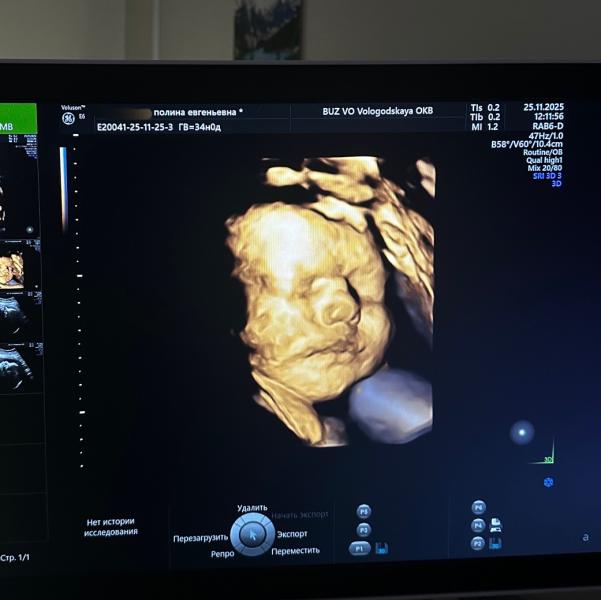

post image 2

Наша щекастая мадама🩶 34 недельки ровно.

Сегодня с нас сняли диагноз «маловесный плод»! 🎉

2094гр